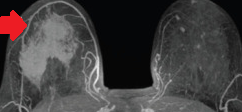

MRI μαστογραφία. Ετερογενής ενισχυμένη πρόσληψη γαδολινίου στον δεξιό μαστό (Ευγενική παραχώρηση Dr. V. Penopoulos)